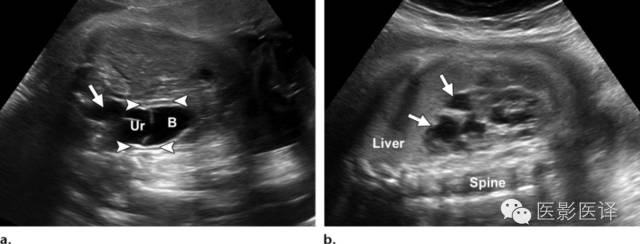

Nussbaum等最早将新生儿卵巢囊肿分为单纯性和复杂性。单纯性卵巢囊肿是圆的、无回声的、单房和薄壁的(图1)。它们更经常为单侧而非双侧、更经常为腹内而非盆腔内。单纯性囊肿内偶尔可见单个分隔(图2)。直径小于20mm的卵巢囊性结构被认为是成熟卵泡,为生理性而非病理性。直径大于20mm的囊肿则考虑为异常。“子囊”征描述的是囊内一个小的、圆形、无回声结构(图3)。既往报道认为这是卵巢囊肿的特征。【在一个23例囊性病变的研究中(包括新生儿、婴儿及儿童),11例发现子囊,占卵巢囊肿的82%(敏感度82%,特异度100%,阳性预测值100%),在其他囊性病变中未发现子囊,包括淋巴管瘤、肠重复畸形、肠囊肿、胎粪假性囊肿、阴道积液和脐尿管囊肿。】

图1:单纯性卵巢囊肿。冠状位胎儿超声图像显示一个边界清楚的薄壁无回声囊肿(箭),高于膀胱(B)位于腹内中线之外。关注脐动脉(箭头)在膀胱两侧。

图2:有单分隔的卵巢囊肿:轴位胎儿超声图像显示一个边界清楚有单一薄壁分隔的(箭)腹内囊肿。囊肿位于膀胱外侧,并在其他图像中显示独立于肾脏和胃肠道。超声多普勒图像(未展示)提示囊肿内无血管。RT=右侧,Sp=脊柱。

图3:单纯性卵巢囊肿。(a)矢状位胎儿超声图像显示一个边界清楚薄壁腹内囊肿(箭头),其内可见一个子囊(箭)。囊肿位于膀胱(B)上方腹中线区。Uv=脐静脉。(b)同一病人轴位超声多普勒图像显示在薄壁卵巢囊肿中有两个子囊(箭头)